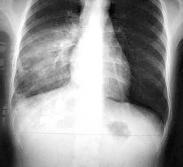

急性嗜酸性粒細胞性肺炎(acute eosinophilic pneumonia,AEP)于1989年首先報道。因其不同于單純性肺嗜酸性粒細胞浸潤癥,因此近年來將其作為一個獨立的臨床病癥。

- 常見癥狀:葉間裂常呈弧形下墜、稽留熱、肺下葉周圍呈節段性或大葉性模糊陰影、高熱寒戰、肺部可聞及干濕啰音及哮鳴音、發燒、肺部化膿性感染、中性粒細胞增高、胸片示肺內孤立結節、煩躁不安、身痛、氣管受壓